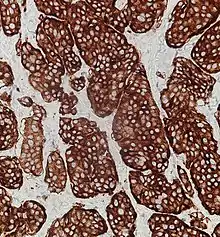

Placing a given tumor into one of these categories depends on well-defined histological features: size, lymphovascular invasion, mitotic count, Ki-67 labelling index, invasion of adjacent organs, presence of metastases and whether they produce hormones.[4][5]

Neuroendocrine tumors, despite differing embryological origin, have common phenotypic characteristics. NETs show tissue immunoreactivity for markers of neuroendocrine differentiation (pan-neuroendocrine tissue markers) and may secrete various peptides and hormones. There is a lengthy list of potential markers in neuroendocrine tumors; several reviews provide assistance in understanding these markers.[70][60] Widely used neuroendocrine tissue markers are various chromogranins, synaptophysin and PGP9.5. Neuron-specific enolase (NSE) is less specific.[1][8] The nuclear neuroendocrine marker insulinoma-associated protein-1 (INSM1) has proven to be sensitive as well as highly specific for neuroendocrine differentiation.[71]

Some neuroendocrine tumor cells possess especially strong hormone receptors, such as somatostatin receptors and uptake hormones strongly. This avidity can assist in diagnosis and may make some tumors vulnerable to hormone targeted therapies.